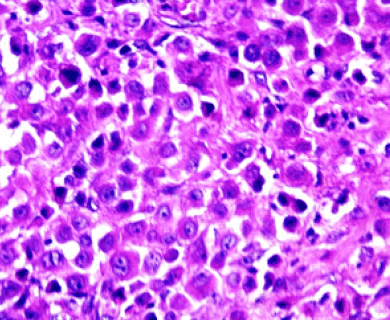

Pathologists look at tumor and tissue samples and determine what cells they can see. If the majority of cells from your mesothelioma sample are epithelioid cells, your mesothelioma subtype is determined to be epithelioid mesothelioma.

“Epithelioid” and “epithelial” are sometimes used in ways that feel interchangeable. But epithelial cells are normal cells that line the skin and the inside of organs. Epithelioid cells can be found in both cancerous and non-cancerous conditions. Epithelioid cells look like epithelial cells, which are shaped like columns or cubes. However, epithelioid cells may come from different types of cells that have mutated or changed shape, taking on an appearance similar to epithelial cells.

Epithelioid mesothelioma cells clump together in groups and don’t tend to travel. These cell types are less likely to spread to other areas of the body. When a pathologist confirms the presence of specific cancer cells, an accurate diagnosis of your mesothelioma type can be made.

The tool or technique for studying cancer tissues is called immunohistochemistry. Pathologists look at stained samples, testing for certain proteins linked to epithelial cells. If pathologists find proteins from other cancers, they’ll rule out epithelioid mesothelioma.

The proteins that help doctors identify epithelioid mesothelioma from different types of cancer include: calretinin, D2-40, keratin 5/6, podoplanin and WT-1 protein. An official diagnosis depends on more than just immunohistochemistry. It also considers the tumor’s appearance, location and cell traits.

While epithelioid is a subtype of mesothelioma, there are further subtypes of the epithelioid type. Pathologists can identify these cell subtypes with immunohistochemistry.